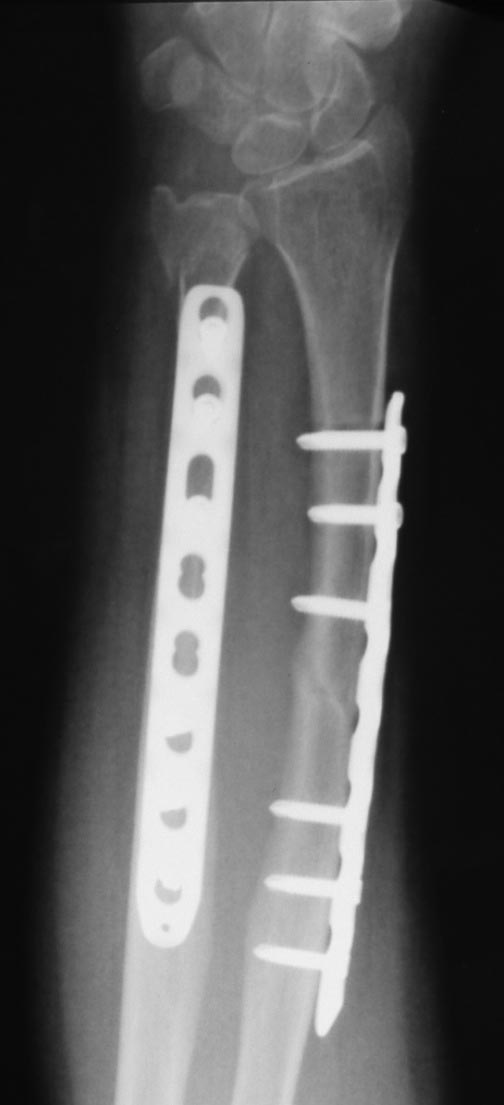

Уважаемые коллеги.Пациентка 45 лет прооперирована по поводу перелома костей предплечья

26.01.12. Послеоперационый период гладкий, функция предплечья восстановилась. 12.05.12

упала повторно (обморок).

Диагностирован перелом головки локтевой кости. На мой взгляд, имеется и перелом по ходу

дистального винта лучевой кости (появилось разрежение вокруг винта, которого не было на

рентгенограммах через 1.5 мес. после операции). Хотя, локальной болезненности в этом месте

нет. Болит в проекции кистевого сустава. Вопрос: показано ли удаление этого винта? Не будет

ли он препятствовать консолидации? Заранее спасибо за ответы.